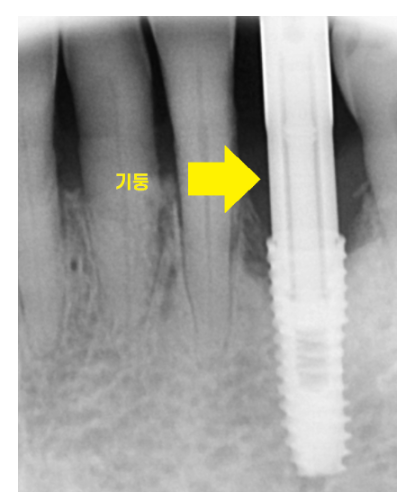

240429 수술까지 완료한 모습은 이렇습니다.

환자분 눈에 보이는 보철까지 완성 되는 것은

또다른 이야기입니다.

임플란트는 뼈와 유착되는 기간이 필요하기 때문에

하루만에 임플란트 머리까지 만드는 것은 어려울 수 있습니다.